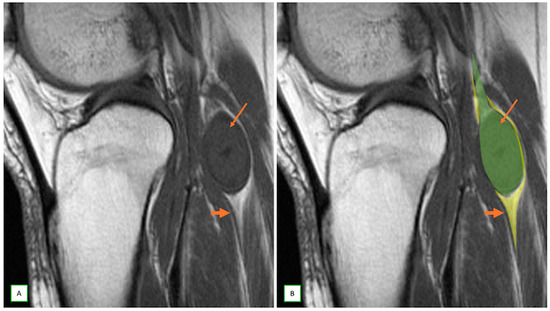

- Primary Sarcomas: Soft-tissue sarcomas are uncommon, accounting for just over 1% of adult malignancies. Synovial sarcoma, clear cell sarcoma, and epithelioid sarcomas are known to involve peripheral nerves. CT/MR reveals a large soft tissue mass with areas of necrosis or calcification and heterogeneous contrast enhancement. F-18 FDG uptake is useful for both tumor staging and treatment assessment (Figure 26, Figure 27 and Figure 28).